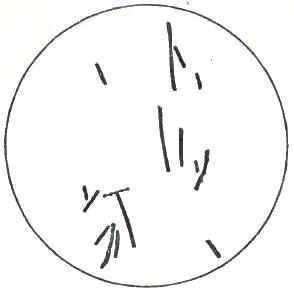

| FIGURE | |

| 1. | MICROCOCCI |

| 2. | BACTERIA |

| 3. | BACILLUS MALARIÆ |

| 4. | BACTERIA FROM GELATIN SOLUTION |

| 5. | VIBRIOS IN GELATIN CULTURE-FLUID |

| 6. | PROTOCOCCUS FROM SLIDES EXPOSED OVER SWAMP-MUD |

| 7. | BACILLI FROM SWAMP-MUD |

| 8. | BACILLI FROM SEPTICÆMIC RABBIT |

| 9. | BACILLI FROM HUMAN SALIVA |

| 10. | BACILLUS ANTHRACIS |

| 11. | BACILLUS TUBERCULOSIS |